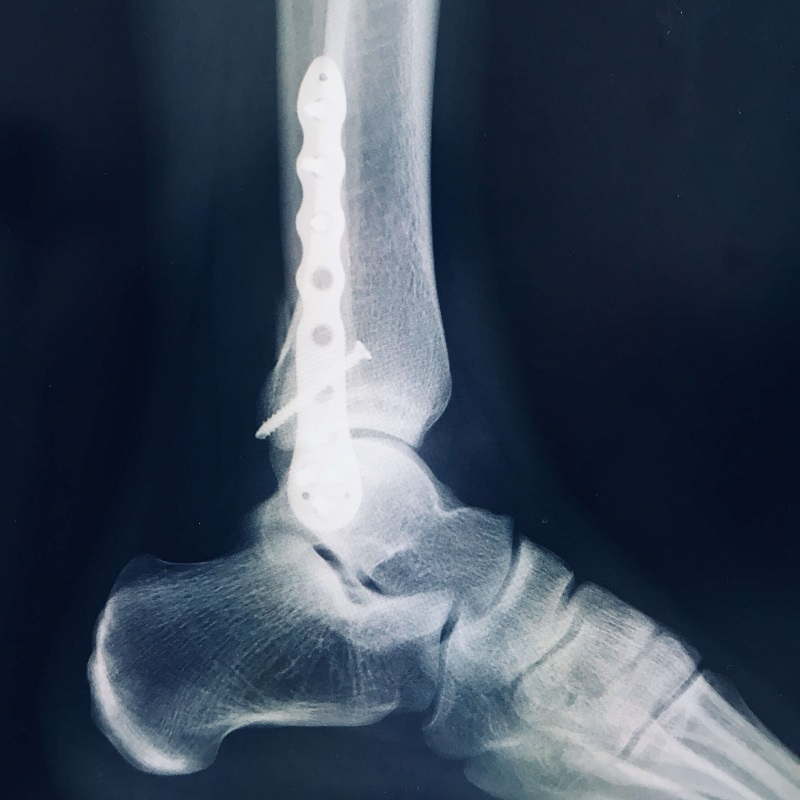

ギブスの代わりに金属プレートを埋め込んだのです。

それがこちらです。

なんと、2×4工法で使う構造用金物みたいなものが

足に入っているではありませんか。

手術後は何があったかはわかっていませんでしたが、

このX線を見て、なんだか痛みを感じるような気がします。